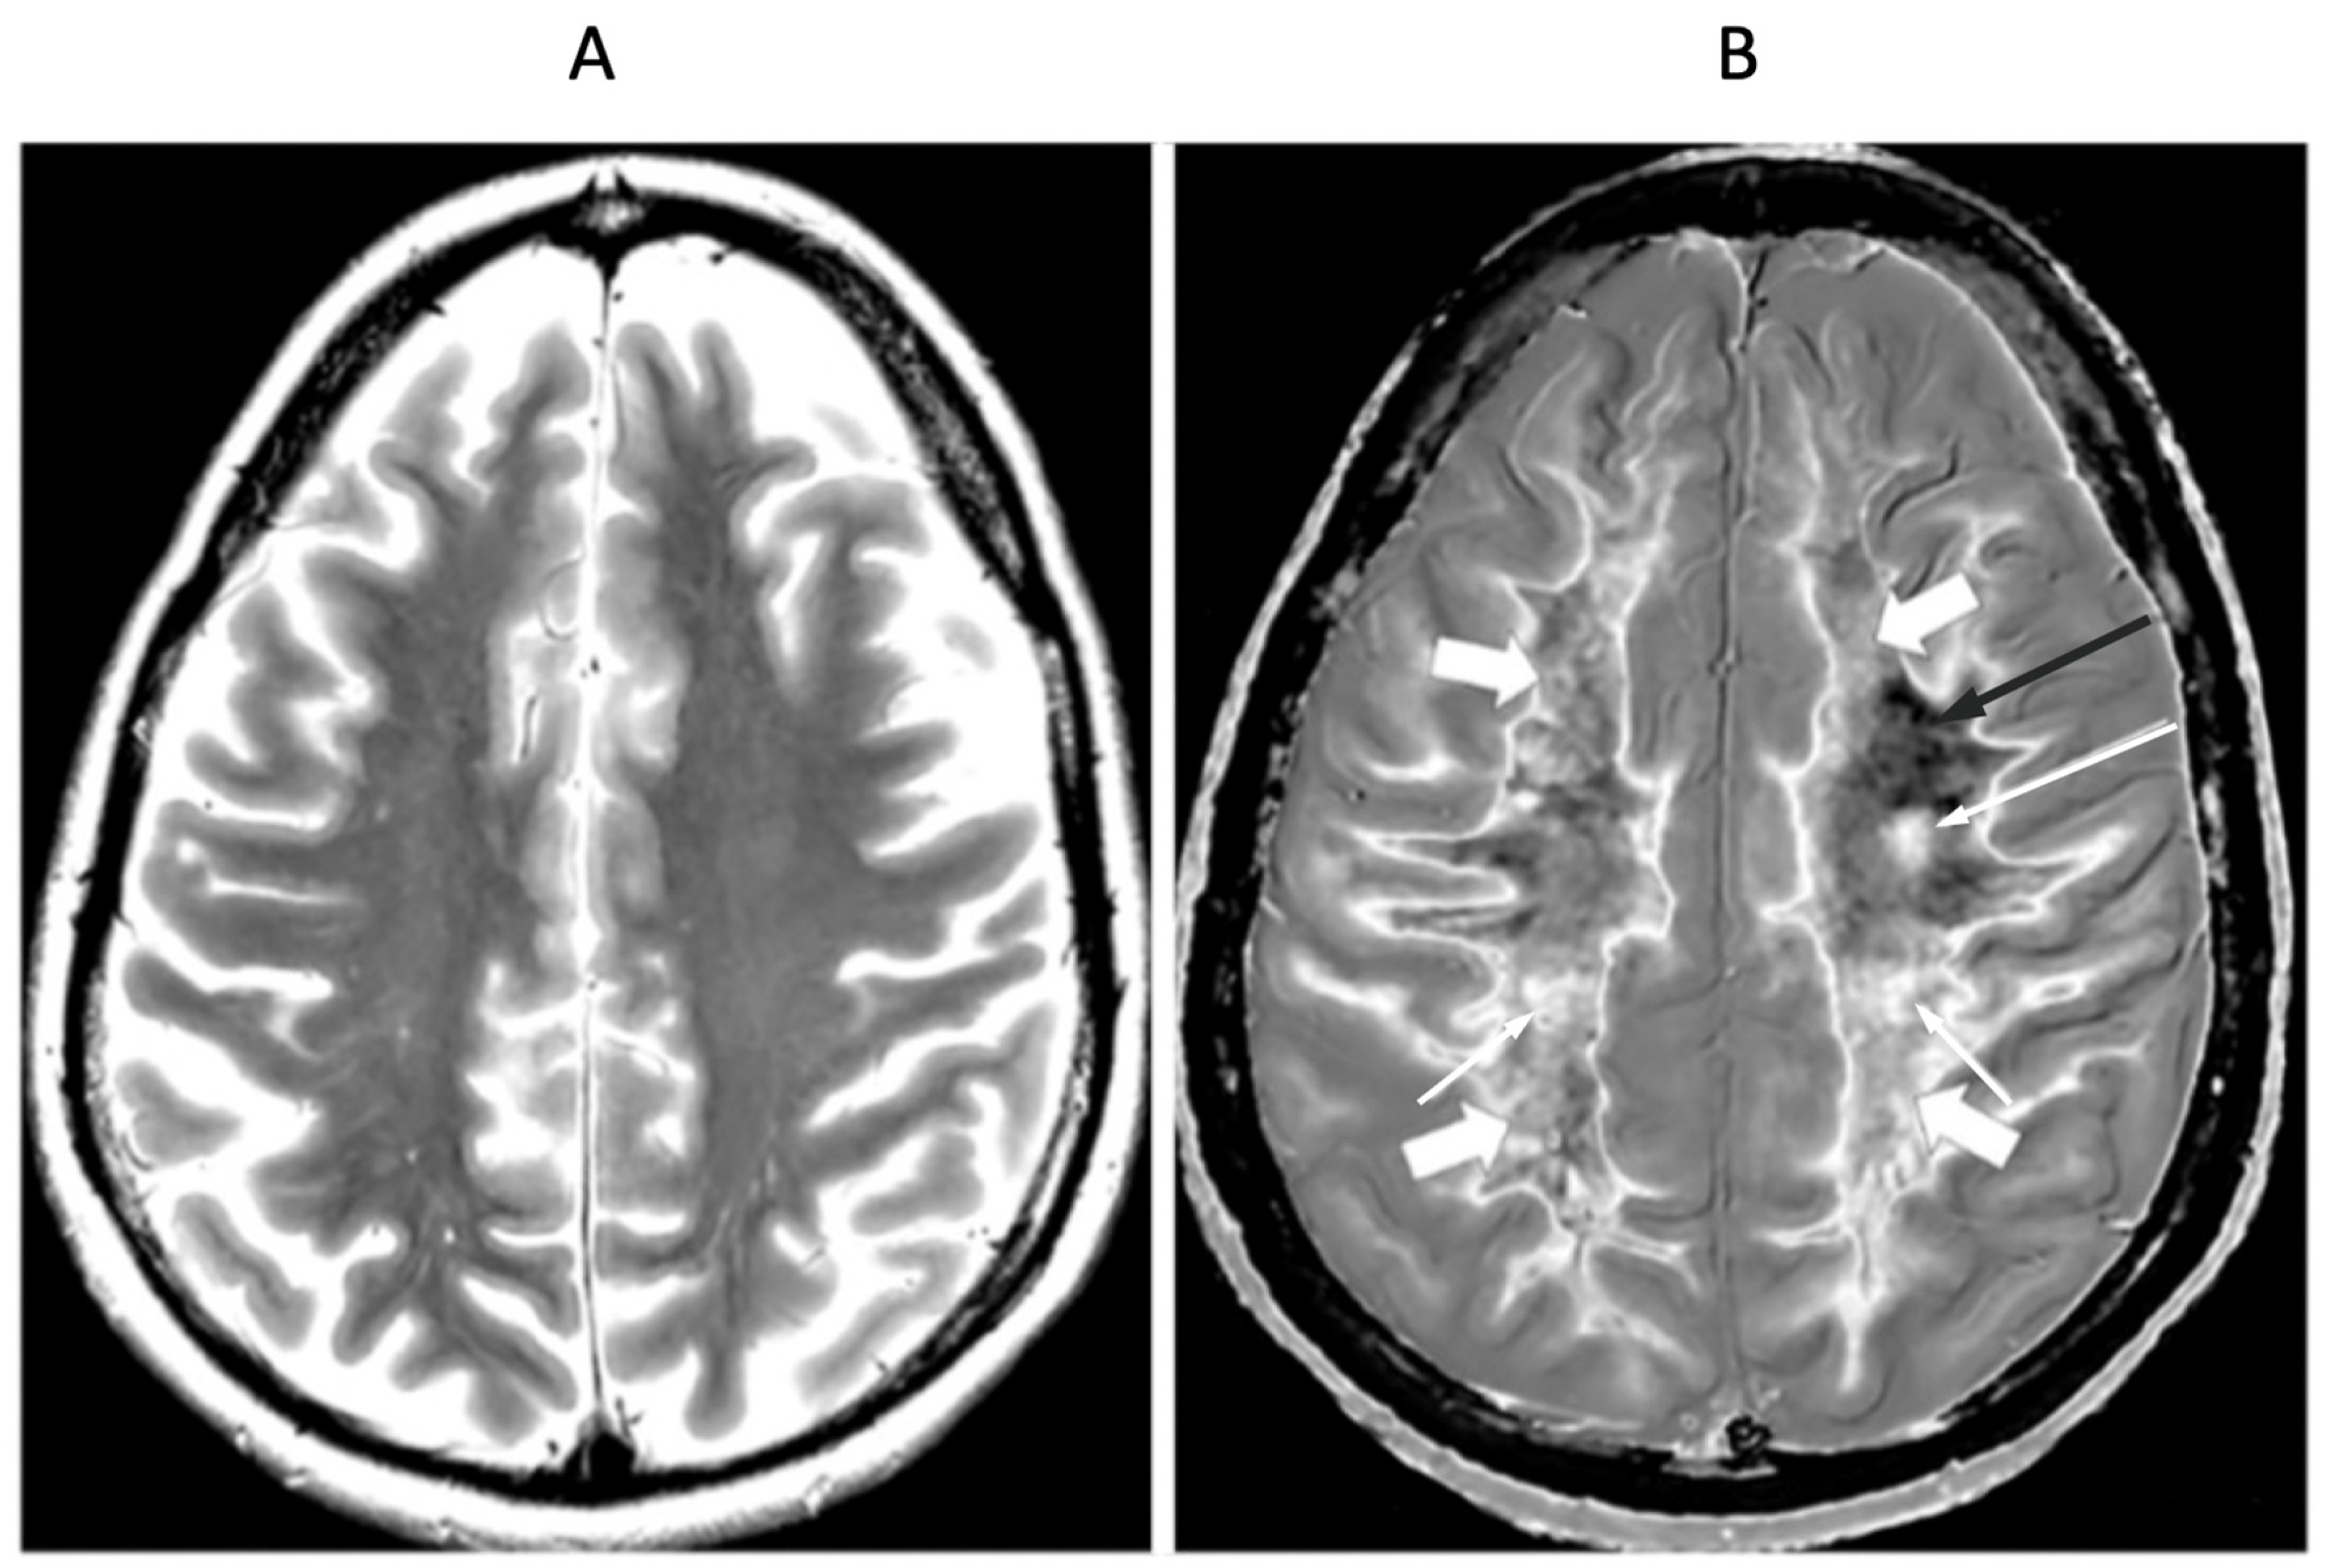

Figure 15.

41-year-old female patient with MS in remission. 2D T2-wSE (A) and narrow mD dSIR (B) images at the same level. No abnormality is seen in (A). A focal lesion is seen in (B) (long narrow white arrow) and the corticospinal tracts show a high signal (short narrow white arrows). In addition there is patchy increased signal in white matter (short thick white arrows) with only a small region showing a normal or near normal low signal appearance (long black arrow). High contrast and high spatial resolution contrast are seen at the boundaries between normal white matter and normal gray matter in (B). These features are less obvious in areas where the white matter has abnormal high signal.